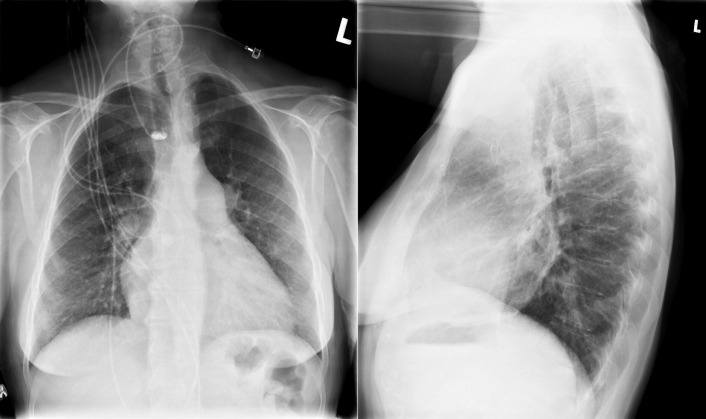

See Figures 18-5 to 18-31 . Possible findings are discussed in the following sections.